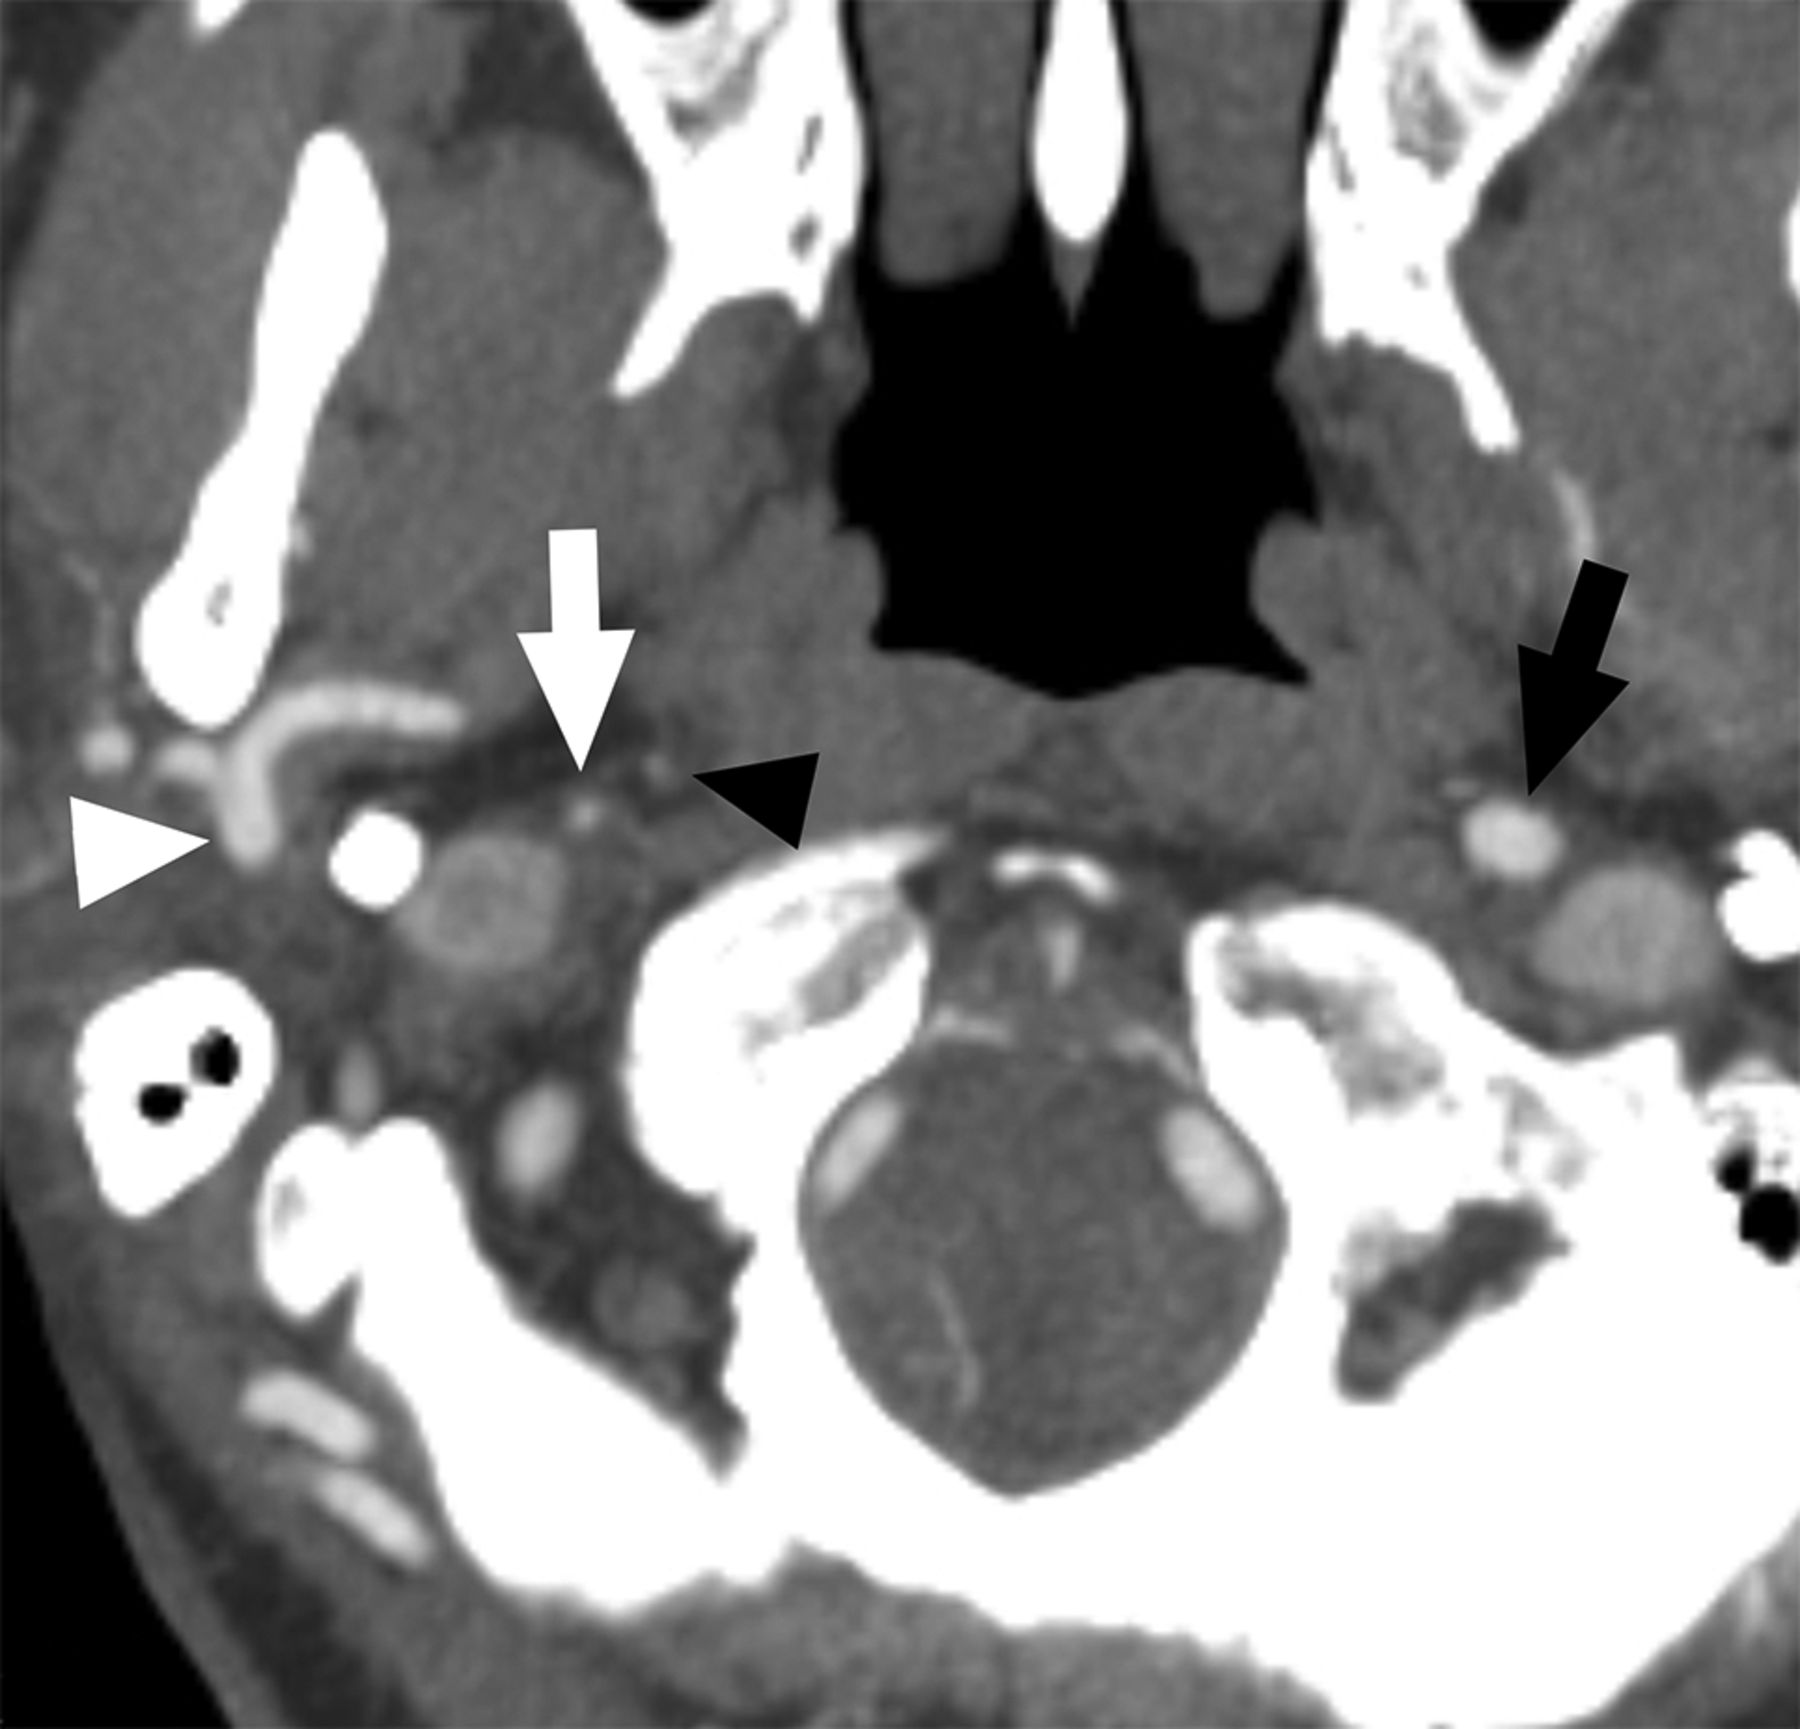

A case with near-occlusion with full collapse. Axial CTA at the level of the distal extracranial ICA. The distal right ICA (white arrow) is clearly collapsed with a threadlike appearance, clearly narrower than the contralateral ICA (black arrow) and the right ECA (white arrowhead). The black arrowhead points to the left ascending pharyngeal artery, ensuring that this is not an ICA occlusion.